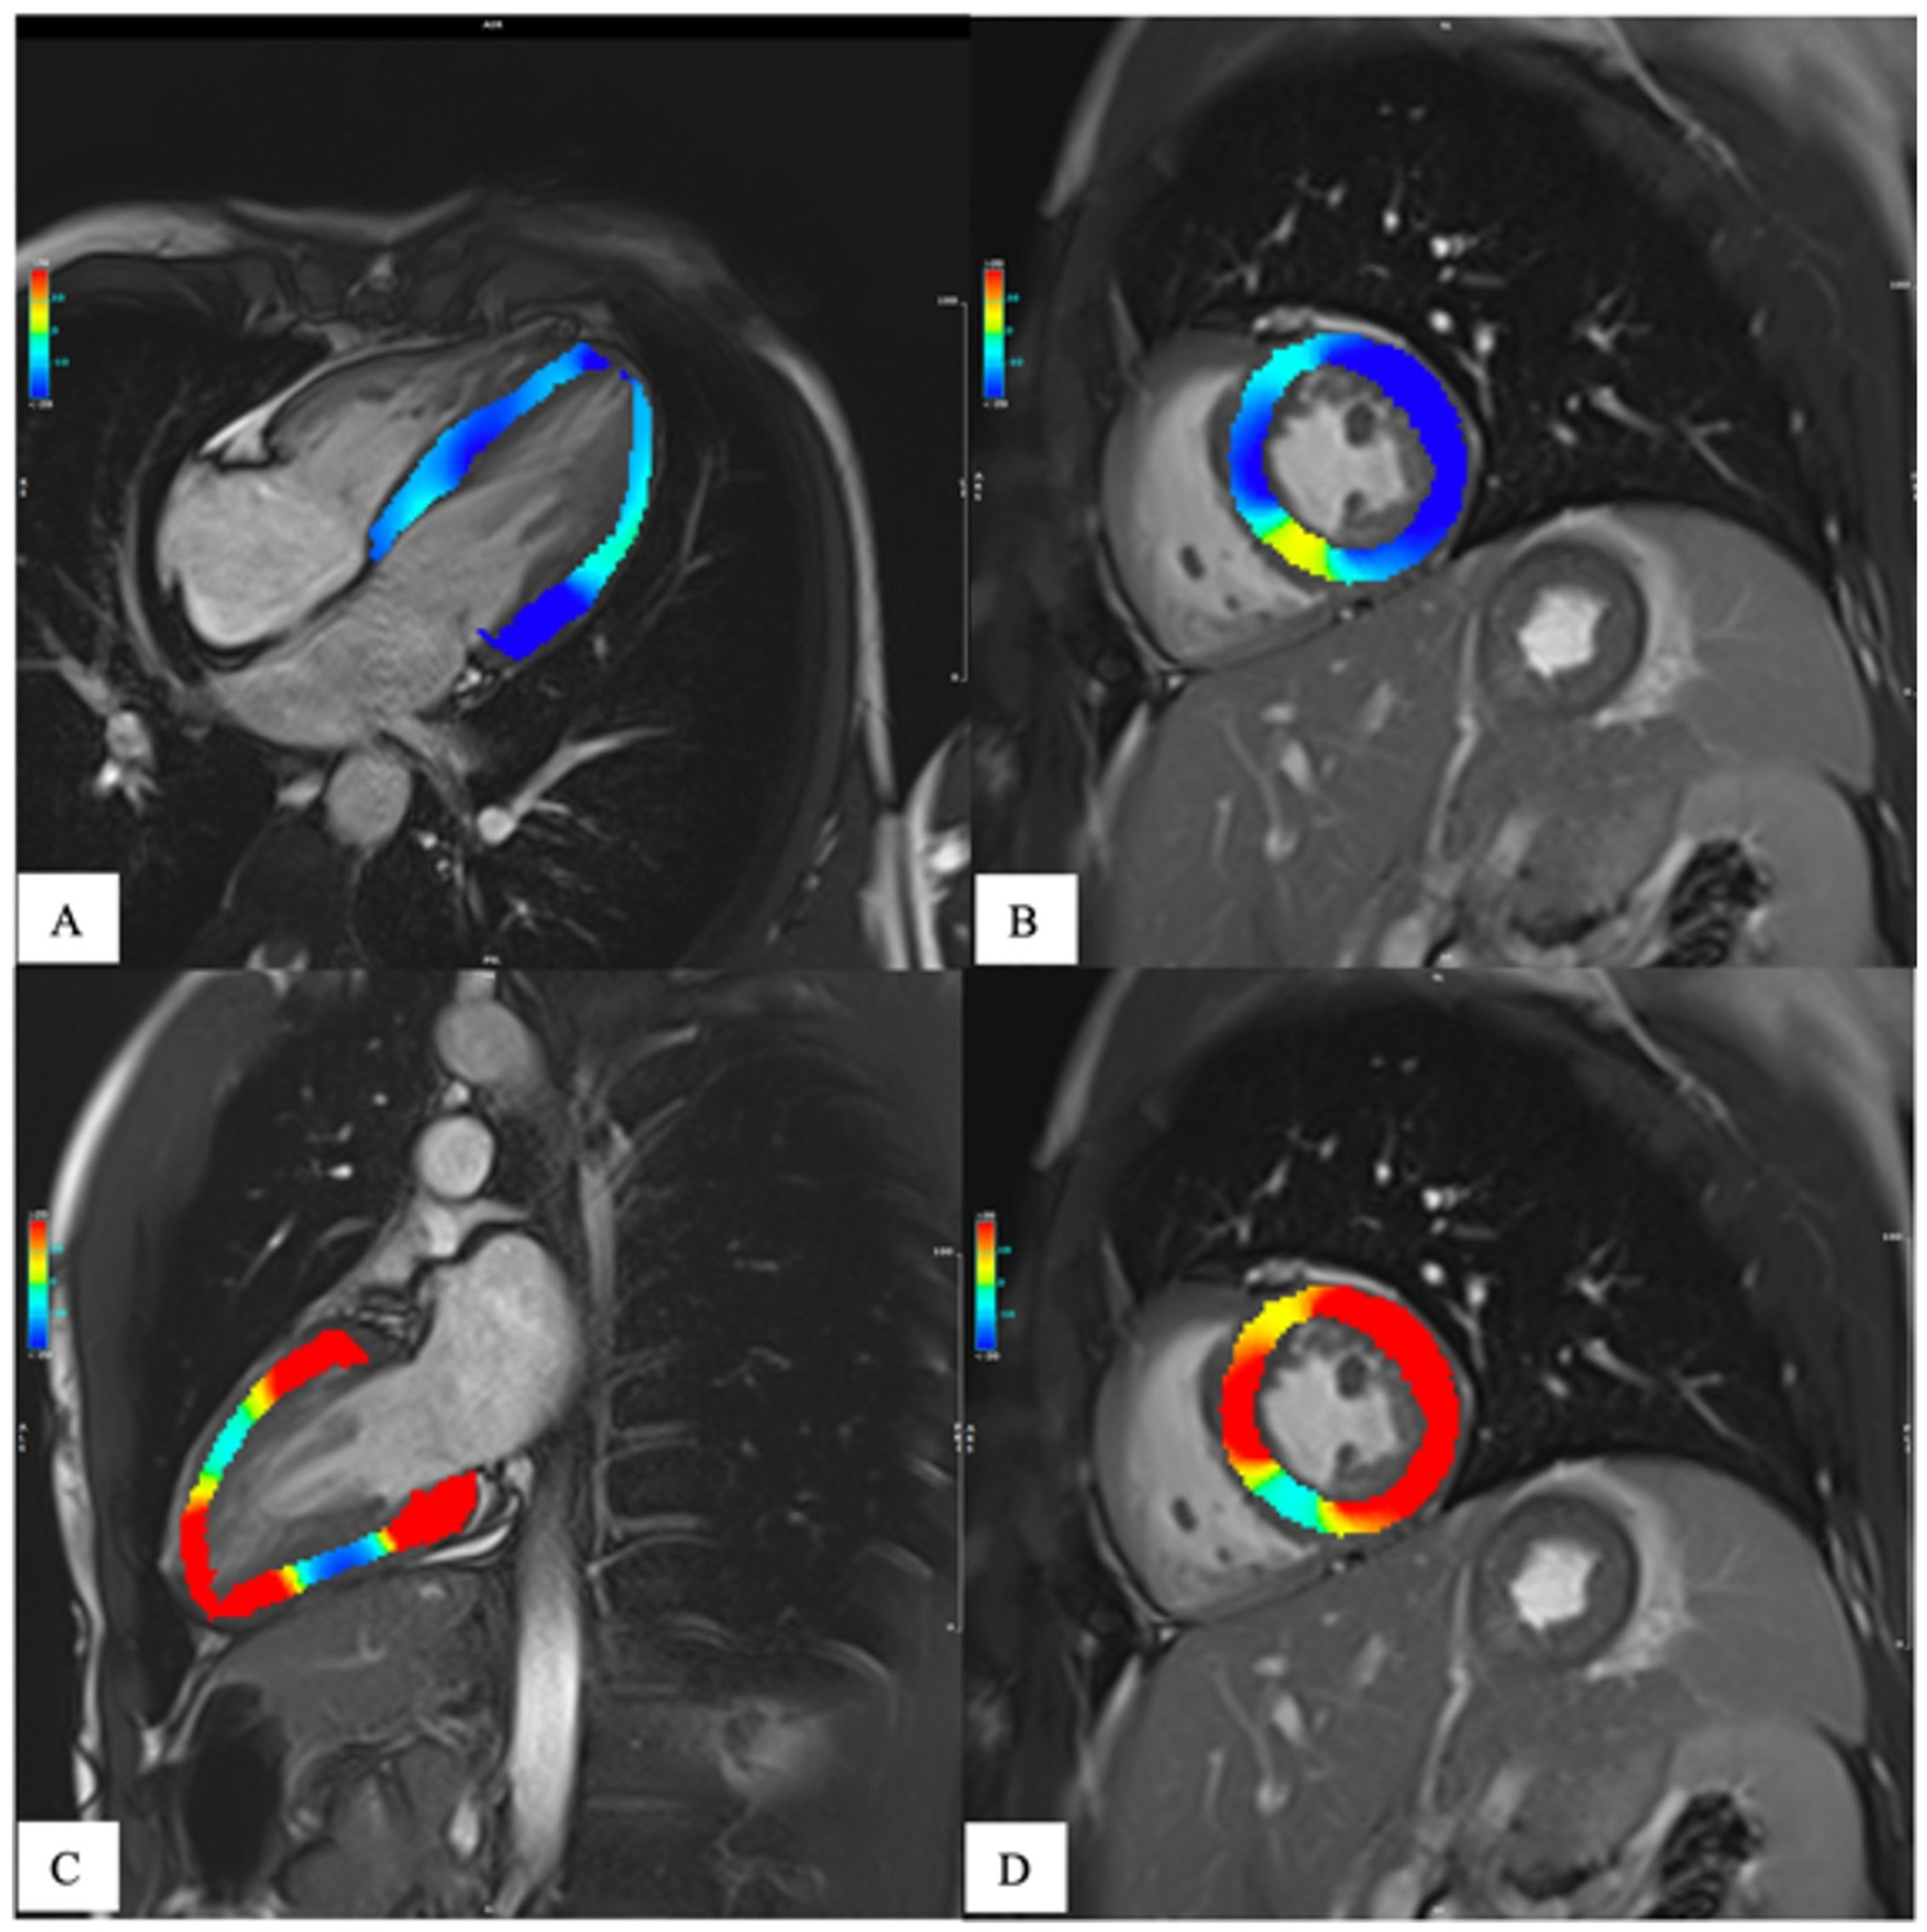

1.2. Magnetic Resonance

- Xu, J.; Yang, W.; Zhao, S.; Lu, M. State-of-the-art myocardial strain by CMR feature tracking: Clinical applications and future perspectives. Eur. Radiol. 2022, 32, 5424–5435. [Google Scholar] [CrossRef] [PubMed]

- Meloni, A.; Gargani, L.; Bruni, C.; Cavallaro, C.; Gobbo, M.; D’Agostino, A.; D’Angelo, G.; Martini, N.; Grigioni, F.; Sinagra, G.; et al. Additional value of T1 and T2 mapping techniques for early detection of myocardial involvement in scleroderma. Int. J. Cardiol. 2023, 376, 139–146. [Google Scholar] [CrossRef]

- Meloni, A.; Pistoia, L.; Positano, V.; Martini, N.; Borrello, R.L.; Sbragi, S.; Spasiano, A.; Casini, T.; Bitti, P.P.; Putti, M.C.; et al. Myocardial tissue characterization by segmental T2 mapping in thalassaemia major: Detecting inflammation beyond iron. Eur. Heart J.-Cardiovasc. Imaging 2023. [Google Scholar] [CrossRef]

- Meloni, A.; Positano, V.; Ruffo, G.B.; Spasiano, A.; D’Ascola, D.G.; Peluso, A.; Keilberg, P.; Restaino, G.; Valeri, G.; Renne, S.; et al. Improvement of heart iron with preserved patterns of iron store by CMR-guided chelation therapy. Eur. Heart J.-Cardiovasc. Imaging 2015, 16, 325–334. [Google Scholar] [CrossRef]

- Pepe, A.; Pistoia, L.; Gamberini, M.R.; Cuccia, L.; Lisi, R.; Cecinati, V.; Maggio, A.; Sorrentino, F.; Filosa, A.; Rosso, R.; et al. National networking in rare diseases and reduction of cardiac burden in thalassemia major. Eur. Heart J. 2022, 43, 2482–2492. [Google Scholar] [CrossRef]